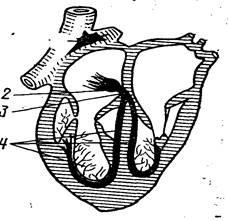

Centrele sistemului de conducere cardiace sunt cele două noduri (Figura 3):

1) atrionector (nodul Flack) dispus în peretele dintre deschiderea venei cave superioare și ale urechii și ale donatorilor dreapta ramuri ale miocardului atrial atriul drept;

2) nodul atrioventricular (nodul Aschoff-Tawara) situată în grosimea inferior diviziunii interatrial sept. Jos acest nod trece la pachetul atrioventricular (pachet de His), care leagă miocardului atrial de la miocardului ventricular. Partea musculară a septului interventricular, această fază este împărțită în dreapta și din stânga picioare. Capătul de ramificare fibrelor (fibre Purkinje) sistemul de conducere cardiace, care se descompun aceste picioare termina in miocard ventriculare.

Fig. 3. Schema sistemului de conducere cardiac

1 - atrionector; 2 - nodul atrioventricular;

3 - trunchi atrioventricular (bloc de ramură); 4 - picioarele și ramificare

Toate aceste componente ale sistemului de conducere formate de celulele musculare atipice, care sunt specializate funcțional sau generarea de impulsuri se propagă prin inimă și provoacă contracția părților sale în secvența dorită și cu o anumită frecvență (celule nodulare) sau holding și transfer de miocite sale contractile.